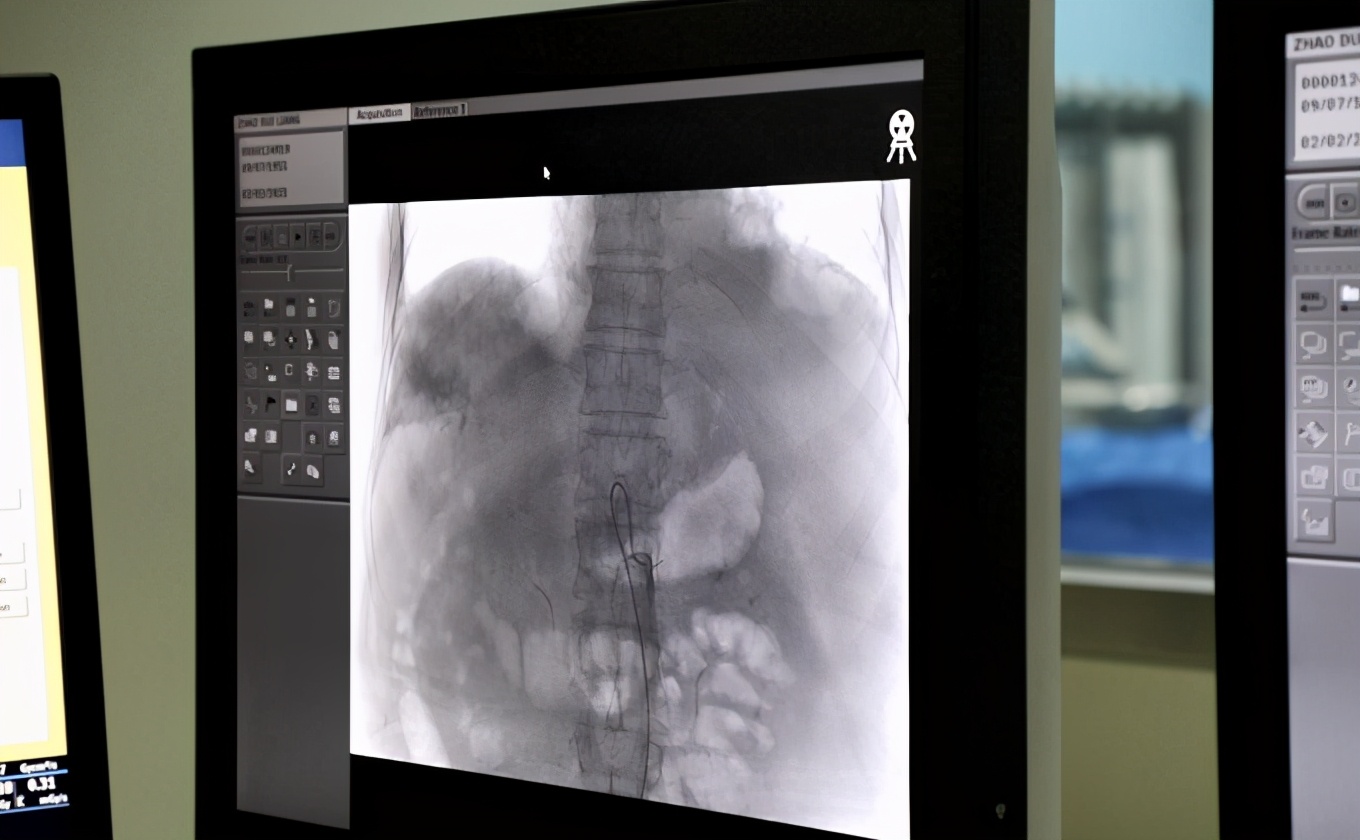

介入医学科也叫不开刀的手术,是在影像的引导下,用导管、导丝、穿刺针等,对体内的病灶进行有效的诊断和治疗。介入治疗,对于过去许多无法治疗,或者必须通过手术治疗,以及内科治疗欠佳的疾病,都有很好的效果。

总体上介入医学分为三个方面。第一是用以诊断,介入放射学可以看到病变的血管特征、组织学、病理学、生化学和微生物学的标本,然后对病变进行进一步的治疗。第二是针对出血性疾病、肿瘤性疾病、栓塞性疾病进行诊断和治疗。第三是对于非血管的病变,比如对食道、胆道、输尿管等管腔性病变进行治疗。还可以对骨肌疾病进行针对性的治疗等等。如果进一步细分,还可以分为神经介入放射学、心脏肌肉介入放射学、外周胶原介入放射学、疼痛介入放射学等等,未来可能还会有更多的专业涌现出来。